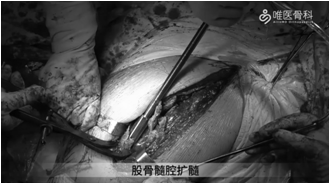

①充分冲洗后给予股骨髓腔扩髓、预绑钢丝,然后安装股骨假体(MP)远端,安装MP假体近端试模。